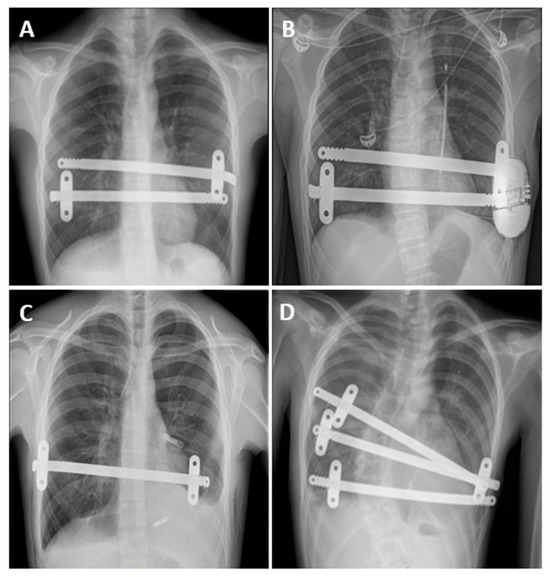

| Case | Age (yr) | HI | Heart Disease | Implantable Medical Devices | ASA | Comorbidities |

|---|---|---|---|---|---|---|

| 1 | 16 | 5 | VF arrest | S-ICD | 3 | - |

| 2 | 15 | 6.8 | MVP | - | 3 | MS, Scoliosis, PA |

| 3 | 21 | 5 | II° AVB | MLP | 3 | ADHD, BD, Asthma |

| 4 | 52 | 4 | Pericarditis | - | 3 | Mondor Syndrome |

| Case | Pectus Technique | Operation Time (min) | Number of Bars Placed | Resection of Costal Cartilage | Wedge Resection of the Sternal Body | Postoperative Complications | Chest Tube Duration (Days) | LOS (Days) |

|---|---|---|---|---|---|---|---|---|

| 1 | Nuss | 80 | 2 | - | - | - | 3 | 28 |

| 2 | Nuss | 455 | 3 | - | - | PAL, fever | 29 | 36 |

| 3 | Nuss | 55 | 1 | - | - | Transitory fever | 4 | 4 |

| 4 | Modified Ravitch + Nuss | 105 | 1 | 6th, 7th, and 8th ribs bilaterally | Yes | AF, Atelectasis | 9 | 11 |